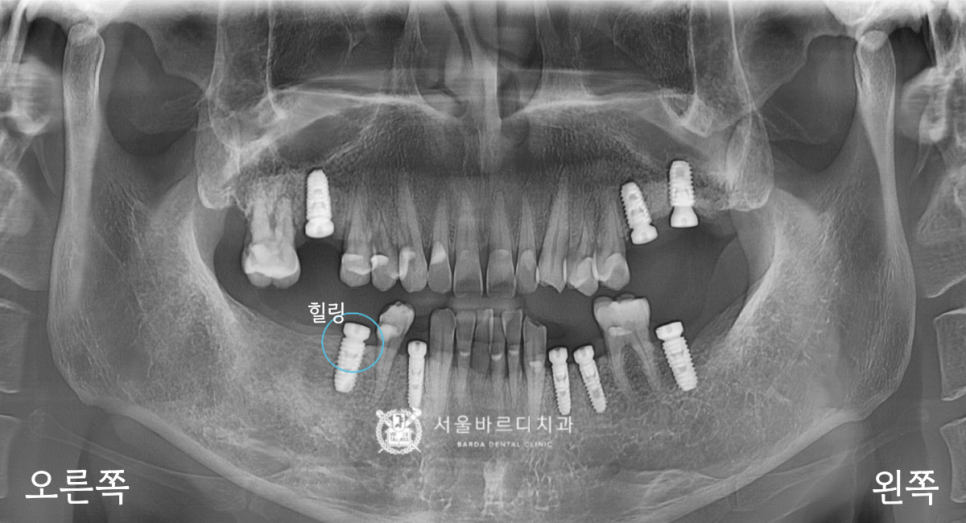

20230629

수술이라는 단어를 사용했지만

납작한 덮개를 긴 뚜껑인 힐링으로 바꿔주는

시술을 이야기하는데요.

이제 기둥과 보철이 들어가기 위해서는

잇몸이 열려있어야 되기 때문에 모양을 잡아주기 위해

힐링(치유지대주)를 넣고, 아물 때까지 기다립니다.